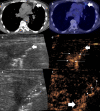

Lung cancer is one of the commonest malignancies worldwide and necessitates both early and personalised treatment. A key requirement is histological sampling with immunohistochemistry obtained usually from percutaneous biopsy. Conventionally thoracic biopsies are performed using CT guidance, but more recently, there has been development of physician led ultrasound biopsy for pleural lesions. Contrast-enhanced ultrasound (CEUS) has been increasingly used in interventional procedures and is able to offer benefits for thoracic biopsies including improving lesional visualisation and characterisation, targeting viable tissue and avoiding critical vascular structures as well as evaluating for the presence of post-procedural complications. This educational review aims to benefits of the role of CEUS in thoracic biopsies.